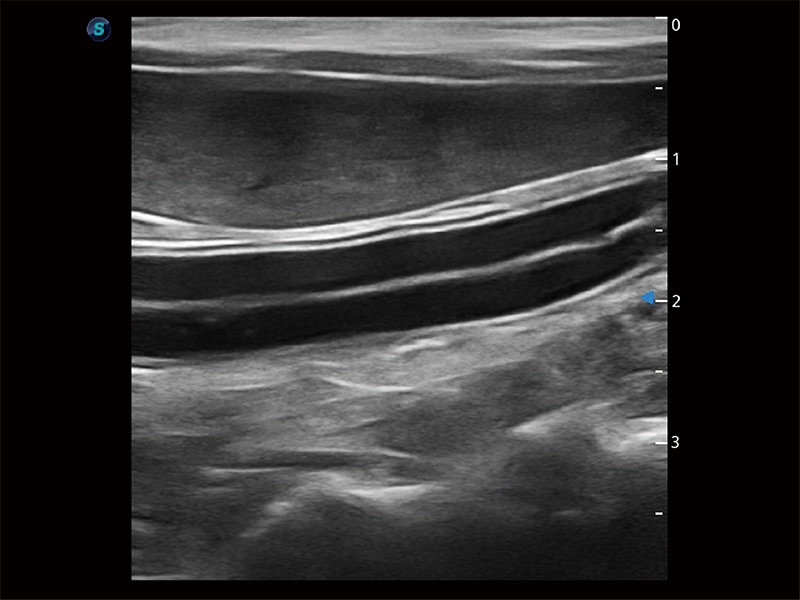

高性能和先进的临床应用工具可以为动物医生提供临床信心。ProPet 80 搭载了先进的腹部和浅表应用工具,帮助医生在日常临床实践中发挥前所未有的作用。

极大提升超低速微细血流的检出能力,同时更精准地滤除软组织和超声信号,为兽用医生提供以往无法通过常规血流获得的疾病诊断信息。

在传统二维血流成像的基础上,呈现血流的立体感,具有动感的生命力之美。即便是微小的血管也能轻松应对,提高了血流的视觉敏感性。

操作简便,无需高频度外力作用即可真实反映组织的形变,快速评估肿瘤良恶性。